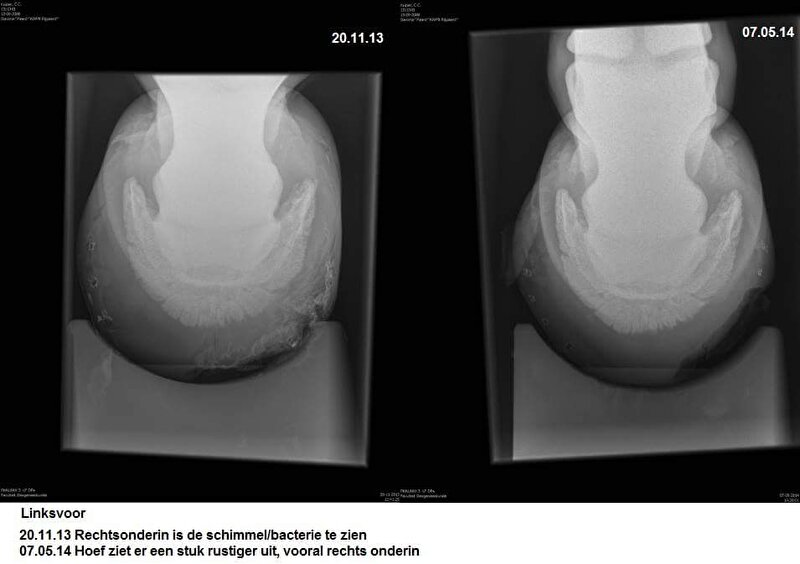

Hier nog wel wat foto's van haar herstel:

Cardy @ [BEH] White Line Disease.. al 12 weken uit de running. Ervaring?